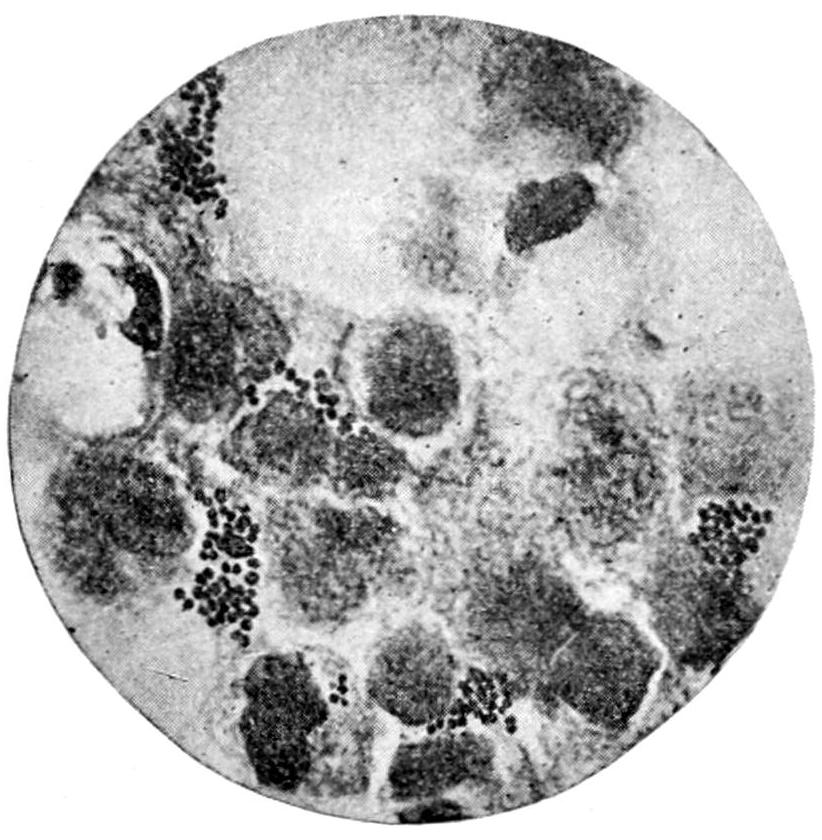

PLATE I

Fig. I.

Fig. II.

Fig. III.

Fig. IV.

Fig. V.

Fig. VI.

Fig. VII.

Fig. VIII.

DRAWN BY J. N. Z. CHASE

PLATE I.

BLOOD.

(Ehrlich triple stain.)

(Prepared by Dr. I. P. Lyon.)

Fig. I. TYPES OF LEUCOCYTES.

a. Polymorphonuclear Neutrophile. b. Polymorphonuclear Eosinophile. c. Myelocyte (Neutrophilic). d. Eosinophilic Myelocyte. e. Large Lymphocyte (large Mononuclear). f. Small Lymphocyte (small Mononuclear).

Fig. II. NORMAL BLOOD.

Field contains one neutrophile. Reds are normal.

Fig. III. ANÆMIA, POST-OPERATIVE (secondary).

The reds are fewer than normal, and are deficient in hæmoglobin and somewhat irregular in form. One normoblast is seen in the field, and two neutrophiles and one small lymphocyte, showing a marked post-hæmorrhagic anæmia, with leucocytosis.

Fig. IV. LEUCOCYTOSIS, INFLAMMATORY.

The reds are normal. A marked leucocytosis is shown, with five neutrophiles and one small lymphocyte. This illustration may also serve the purpose of showing the leucocytosis of malignant tumor.

Fig. V. TRICHINOSIS.

A marked leucocytosis is shown, consisting of an eosinophilia.

Fig. VI. LYMPHATIC LEUKÆMIA.

Slight anæmia. A large relative and absolute increase of the lymphocytes (chiefly the small lymphocytes) is shown.

Fig. VII. SPLENO-MYELOGENOUS LEUKÆMIA.

The reds show a secondary anæmia. Two normoblasts are shown. The leucocytosis is massive. Twenty leucocytes are shown, consisting of nine neutrophiles, seven myelocytes, two small lymphocytes, one eosinophile (polymorphonuclear) and one eosinophilic myelocyte. Note the polymorphous condition of the leucocytes, i. e., their variations from the typical in size and form.

Fig. VIII. VARIETIES OF RED CORPUSCLES.

a. Normal Red Corpuscle (normocyte). b, c. Anæmic Red Corpuscles. d-g. Poikilocytes. h. Microcyte. i. Megalocyte. j-n. Nucleated Red Corpuscles. j, k. Normoblasts. l. Microblast. m, n. Megaloblasts.

The value of a careful blood examination is well illustrated by Plate I, prepared by Dr. Irving P. Lyon, in which are displayed the alterations of greatest interest to the surgeon.